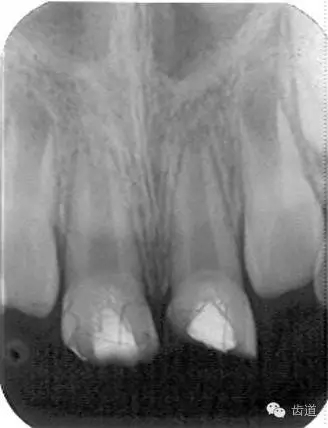

3個(gè)月左右在X線片上可觀察到修復(fù)性牙本質(zhì)層的出現(xiàn), 術(shù)后6個(gè)月左右,??捎^察到連續(xù)的有一定厚度的修復(fù)性牙本質(zhì)層; 修復(fù)性牙本質(zhì)層的出現(xiàn),是間接牙髓治療成功的重要指征。

牙本質(zhì)橋形成 formation of dental bridge